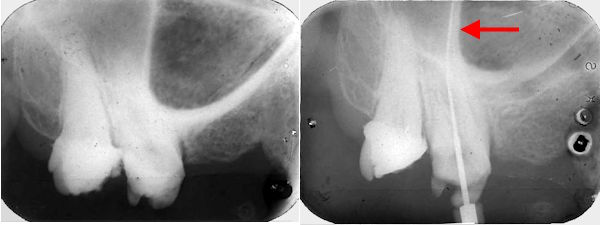

33-jährige Patientin (18.08.1981 / 404)

Bei der Wurzelbehandlung hat eine Nervnadel die Kieferhöhle eröffnet. Auf dem Röntgenbild verdeckt die Kortikalis der Kieferhöhlenwand die Wurzelspitze. Sie befindet sich etwa beim roten Pfeil.

Der Zahnarzt war 29 Jahre alt und entsprechend unerfahren. Er hätte die Körpergrösser der Patientin beachten sollen. Sie ist ca. 1.65 m gross. Da geht man von einer Zahnlänge von 17 mm aus und nicht von 23 mm. Aber so etwas steht wohl in keinem Lehrplan.

33-jährige Patientin (22.02.1982 / 404)

Bei der Wurzelfüllung ist etwas Wurzelfüllmaterial (AH26)über die Wurzelspitze hinausgepresst worden. Das AH26 ist weitgehend keimfrei, liegt auf der Schleimhaut, härtet in 24 h aus und ist ein kleiner Fremdkörper in der Kieferhöhle.